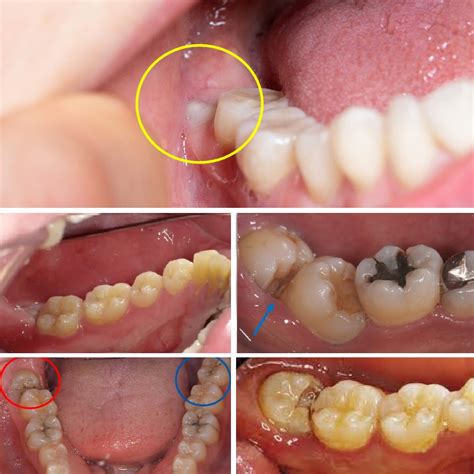

The human mouth is home to a vast microbiome, and when a wisdom tooth is only partially emerged, a flap of gum tissue—known as an operculum—often covers part of the tooth. Bacteria thrive under this flap, leading to a condition called pericoronitis. Identifying the Wisdom Tooth Infection Symptoms early on can be the difference between a simple antibiotic course and the need for more invasive oral surgery.

• picture of infected wisdom tooth